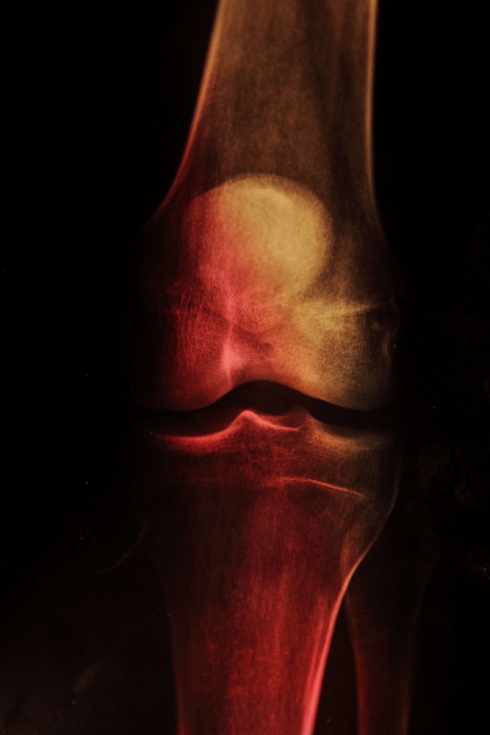

Photo works